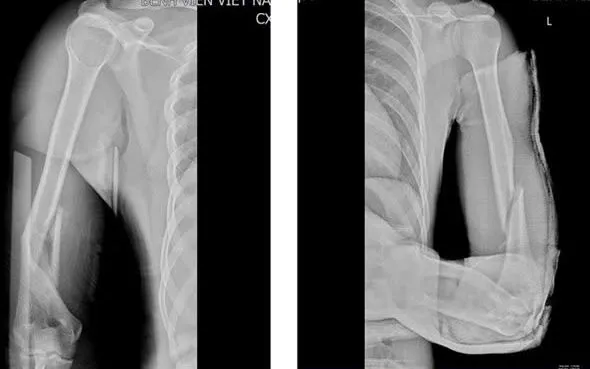

Trong vòng một tuần, Khoa Chấn thương Chỉnh hình & Bỏng, Bệnh viện Việt Nam - Thụy Điển Uông Bí đã tiếp nhận 3 trường hợp nhập viện vì gãy xương cánh tay khi tham gia trò chơi "vật tay". Đây đều là những chấn thương nghiêm trọng, cần can thiệp chuyên sâu.

Theo các bác sĩ, khi vật tay, lực xoay đột ngột và mạnh tác động lên xương cánh tay có thể vượt quá khả năng chịu lực, dẫn đến gãy xoắn xương, thậm chí di lệch. Những trường hợp này buộc phải phẫu thuật kết hợp xương bằng nẹp vít để cố định vững chắc vị trí gãy, rút ngắn thời gian hồi phục và hạn chế biến chứng.

Nhiều bệnh nhân nhập viện trong tình trạng xương gãy nham nhở, gây khó khăn trong việc đưa các mảnh xương về vị trí ban đầu. Đáng lo ngại hơn, gãy xoắn xương cánh tay có nguy cơ cao làm tổn thương dây thần kinh quay, dây thần kinh trụ hoặc mạch máu lân cận, để lại di chứng vận động về sau. Phần lớn ca bệnh thuộc nhóm học sinh, sinh viên - những người thường xem vật tay là một trò thi sức đơn giản, không lường hết rủi ro.